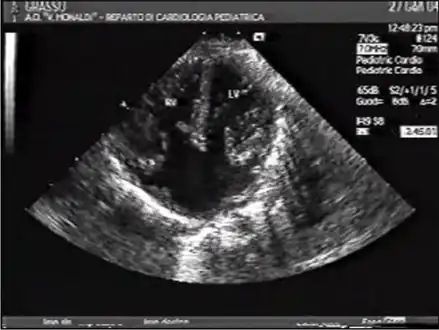

Ultrasound showing a complete atrioventricular septal defect